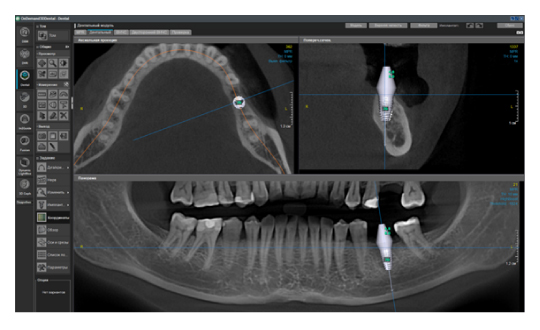

Ещё одна актуальная проблема в современной стоматологии — это огромное количество разных программ просмотровщиков конусно-лучевой компьютерной томографии. Каждый производитель этого ПО старается сделать что-то уникальное, и для конечного доктора это порой усложняет диагностику. Вы привыкли работать в одной программе, а тут уже пришел пациент с КЛКТ исследованием в совершенно незнакомом софте. У меня даже существует отдельный курс по разбору разных программ, чтобы врач всегда мог сориентироваться и провести консультацию. Но если вы решили купить собственный дентальный томограф, то здесь совет брать программу, которая технически удовлетворит все ваши запросы. Стоит помнить о том, что если вы будете проводить исследования не только для нужд своей клиники, но и сторонним, то эта программа не должна быть обрезанной по функционалу, являться простой, русифицированной, а также знакомой и понятной многим. От себя хочу добавить, что советую обращать внимание на возможность использования различных фильтров резкости изображения, изменения толщины среза, возможность построения произвольных кросс-секций на панорамном реформате, а также большой базы имплантатов (рис. 5), и чтобы всё это было доступно не только в лицензии, но и во viewer (просмотровщике, который получает конечный врач).

Рис. 5. Пример программы OnDemand3D. Панорамный реформат с повышенным фильтром резкости, произвольной кросс-секцией, установленным виртуальным имплантатом.